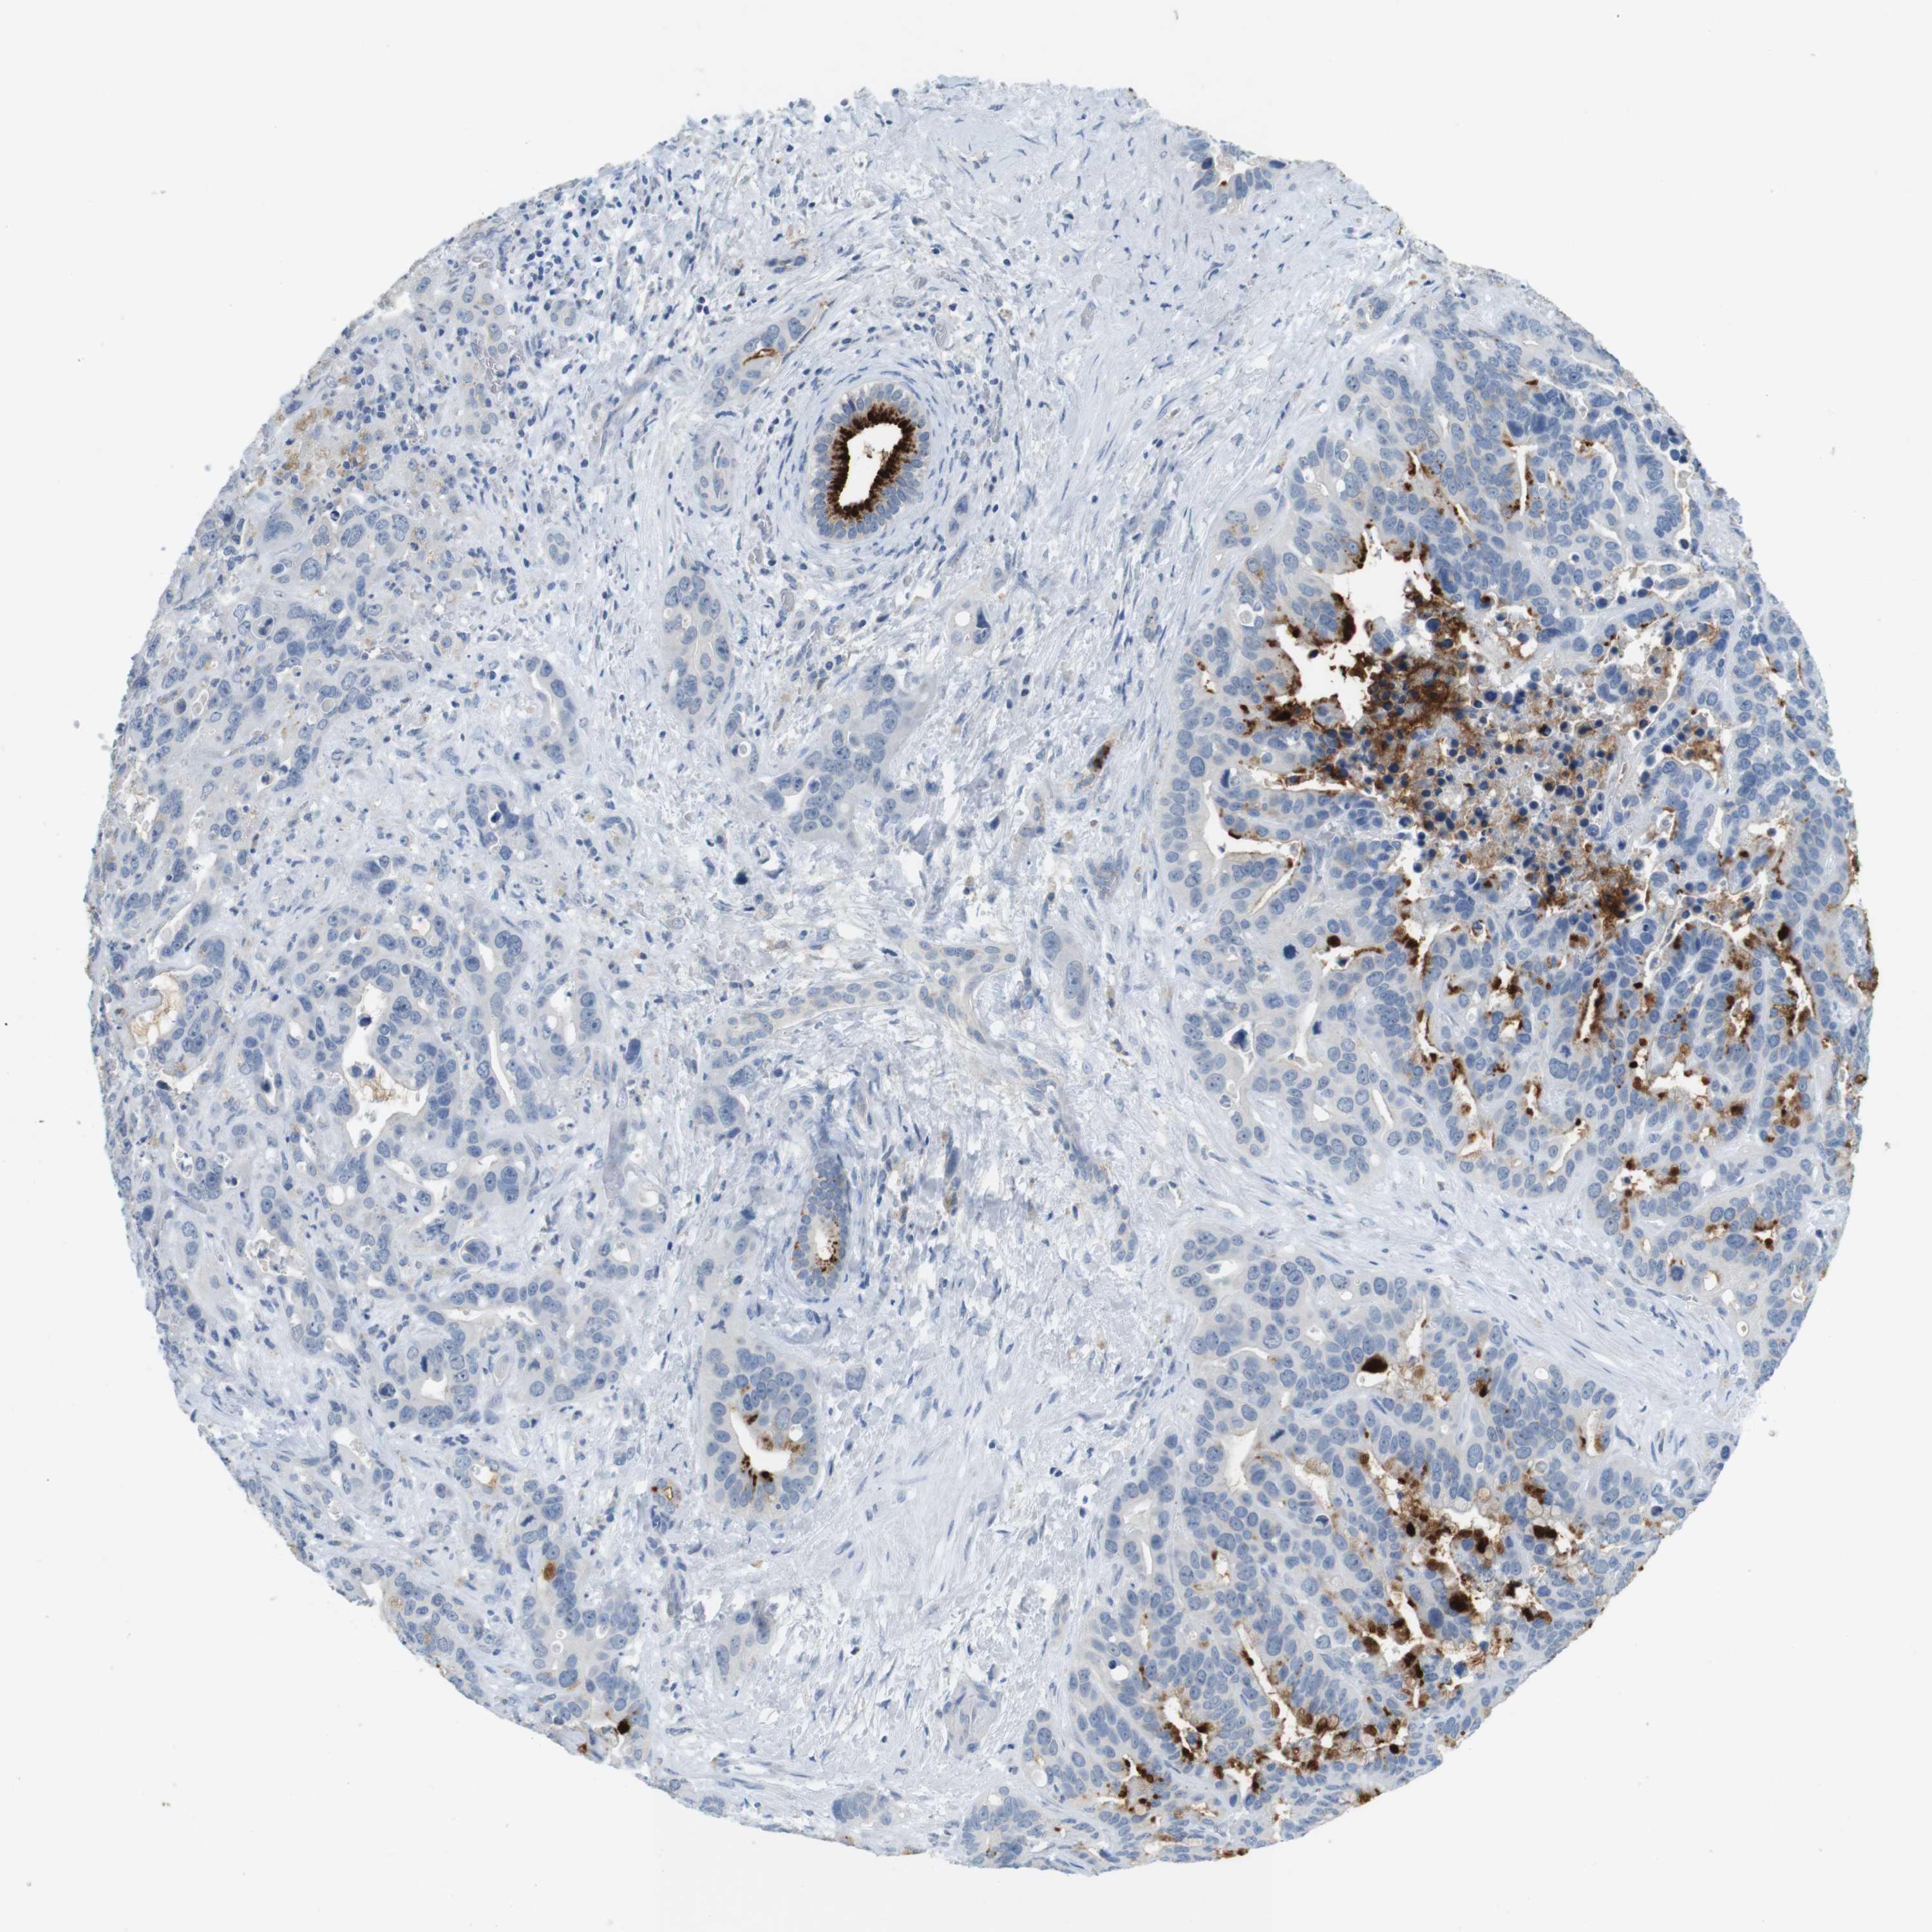

LIVER CANCER - Protein expressioni

A mouse-over function shows sample information and annotation data. Click on an image to view it in a full screen mode. Samples can be filtered based on level of antibody staining by selecting one or several of the following categories: high, medium, low and not detected. The assay and annotation is described here.

Note that samples used for immunohistochemistry by the Human Protein Atlas do not correspond to samples in the TCGA dataset.

Antibody stainingi

Antibody staining in the annotated cell types in the current human tissue is reported as not detected, low, medium, or high, based on conventional immunohistochemistry profiling in selected tissues. This score is based on the combination of the staining intensity and fraction of stained cells.

Each image is clickable and will lead to virtual microscopy that enables deeper exploration of all samples and also displays staining intensity scores, fraction scores and subcellular localization as well as patient and tissue information for each sample.

Antibody HPA008246

Antibody CAB009396

Cholangiocarcinoma

Carcinoma, Hepatocellular, NOS